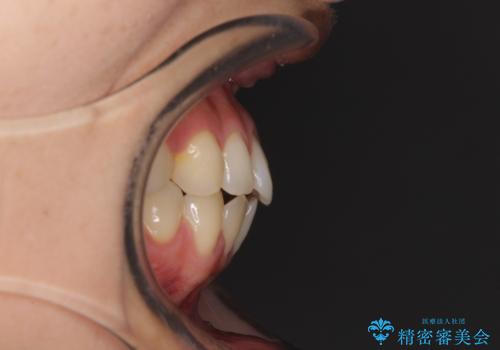

- 前歯の上下スペースと前歯の隙間を気にして来院された患者様です。

飲み込みや話をするときに舌を突出させる癖が強くあり、それが原因でスペースが空いていました。

舌癖を改善するためのトレーニングを行いながら、インビザラインにより上下の前歯の隙間を閉じていくこととしました。